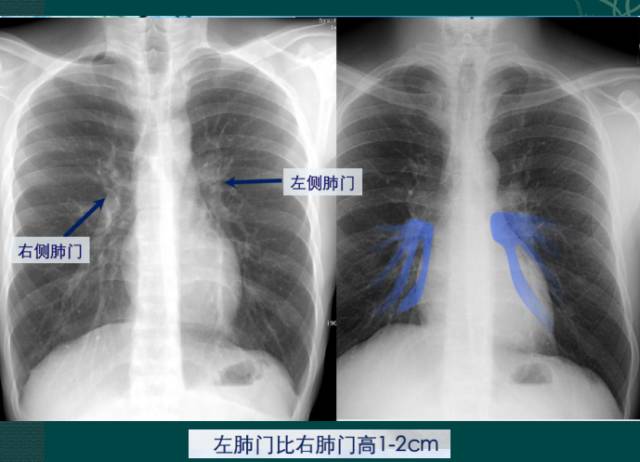

4. 肺门的大小和位置

X线肺门指肺动脉、肺叶动脉、肺段动脉、伴行支气管以及肺静脉构成。

右肺门可分为上、下两部。上部约占1/3,由上肺静脉、上肺动脉及下肺动脉后回归支构成。上肺静脉下后干构成右上肺门的外缘;右肺门下部 约占2/3,由右下肺动脉干构成,其正常宽度不超过15mm,沿中间段支气管外缘平行向外下走行。右肺门上、下部相交形成一钝的夹角,称肺门角,正常该角顶清晰。如下图

左肺门亦分为上、下两部。上部由左肺动脉及其分支、左上叶支气管和左上肺静脉及其分支构成;下部由左下肺动脉及其分支构成,常被心影所遮盖。